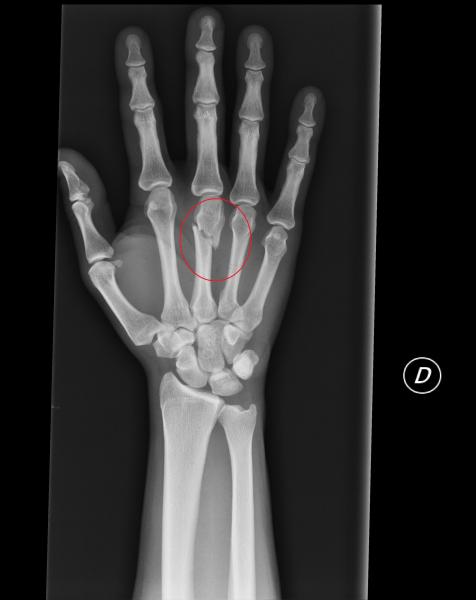

Foto: Dedo roto de uno de los detenidos el 1º de mayo

A las 16.30 han salido el resto de detenidos de la Ciutat de la Justicia. Uno de ellos con los dos brazos rotos.